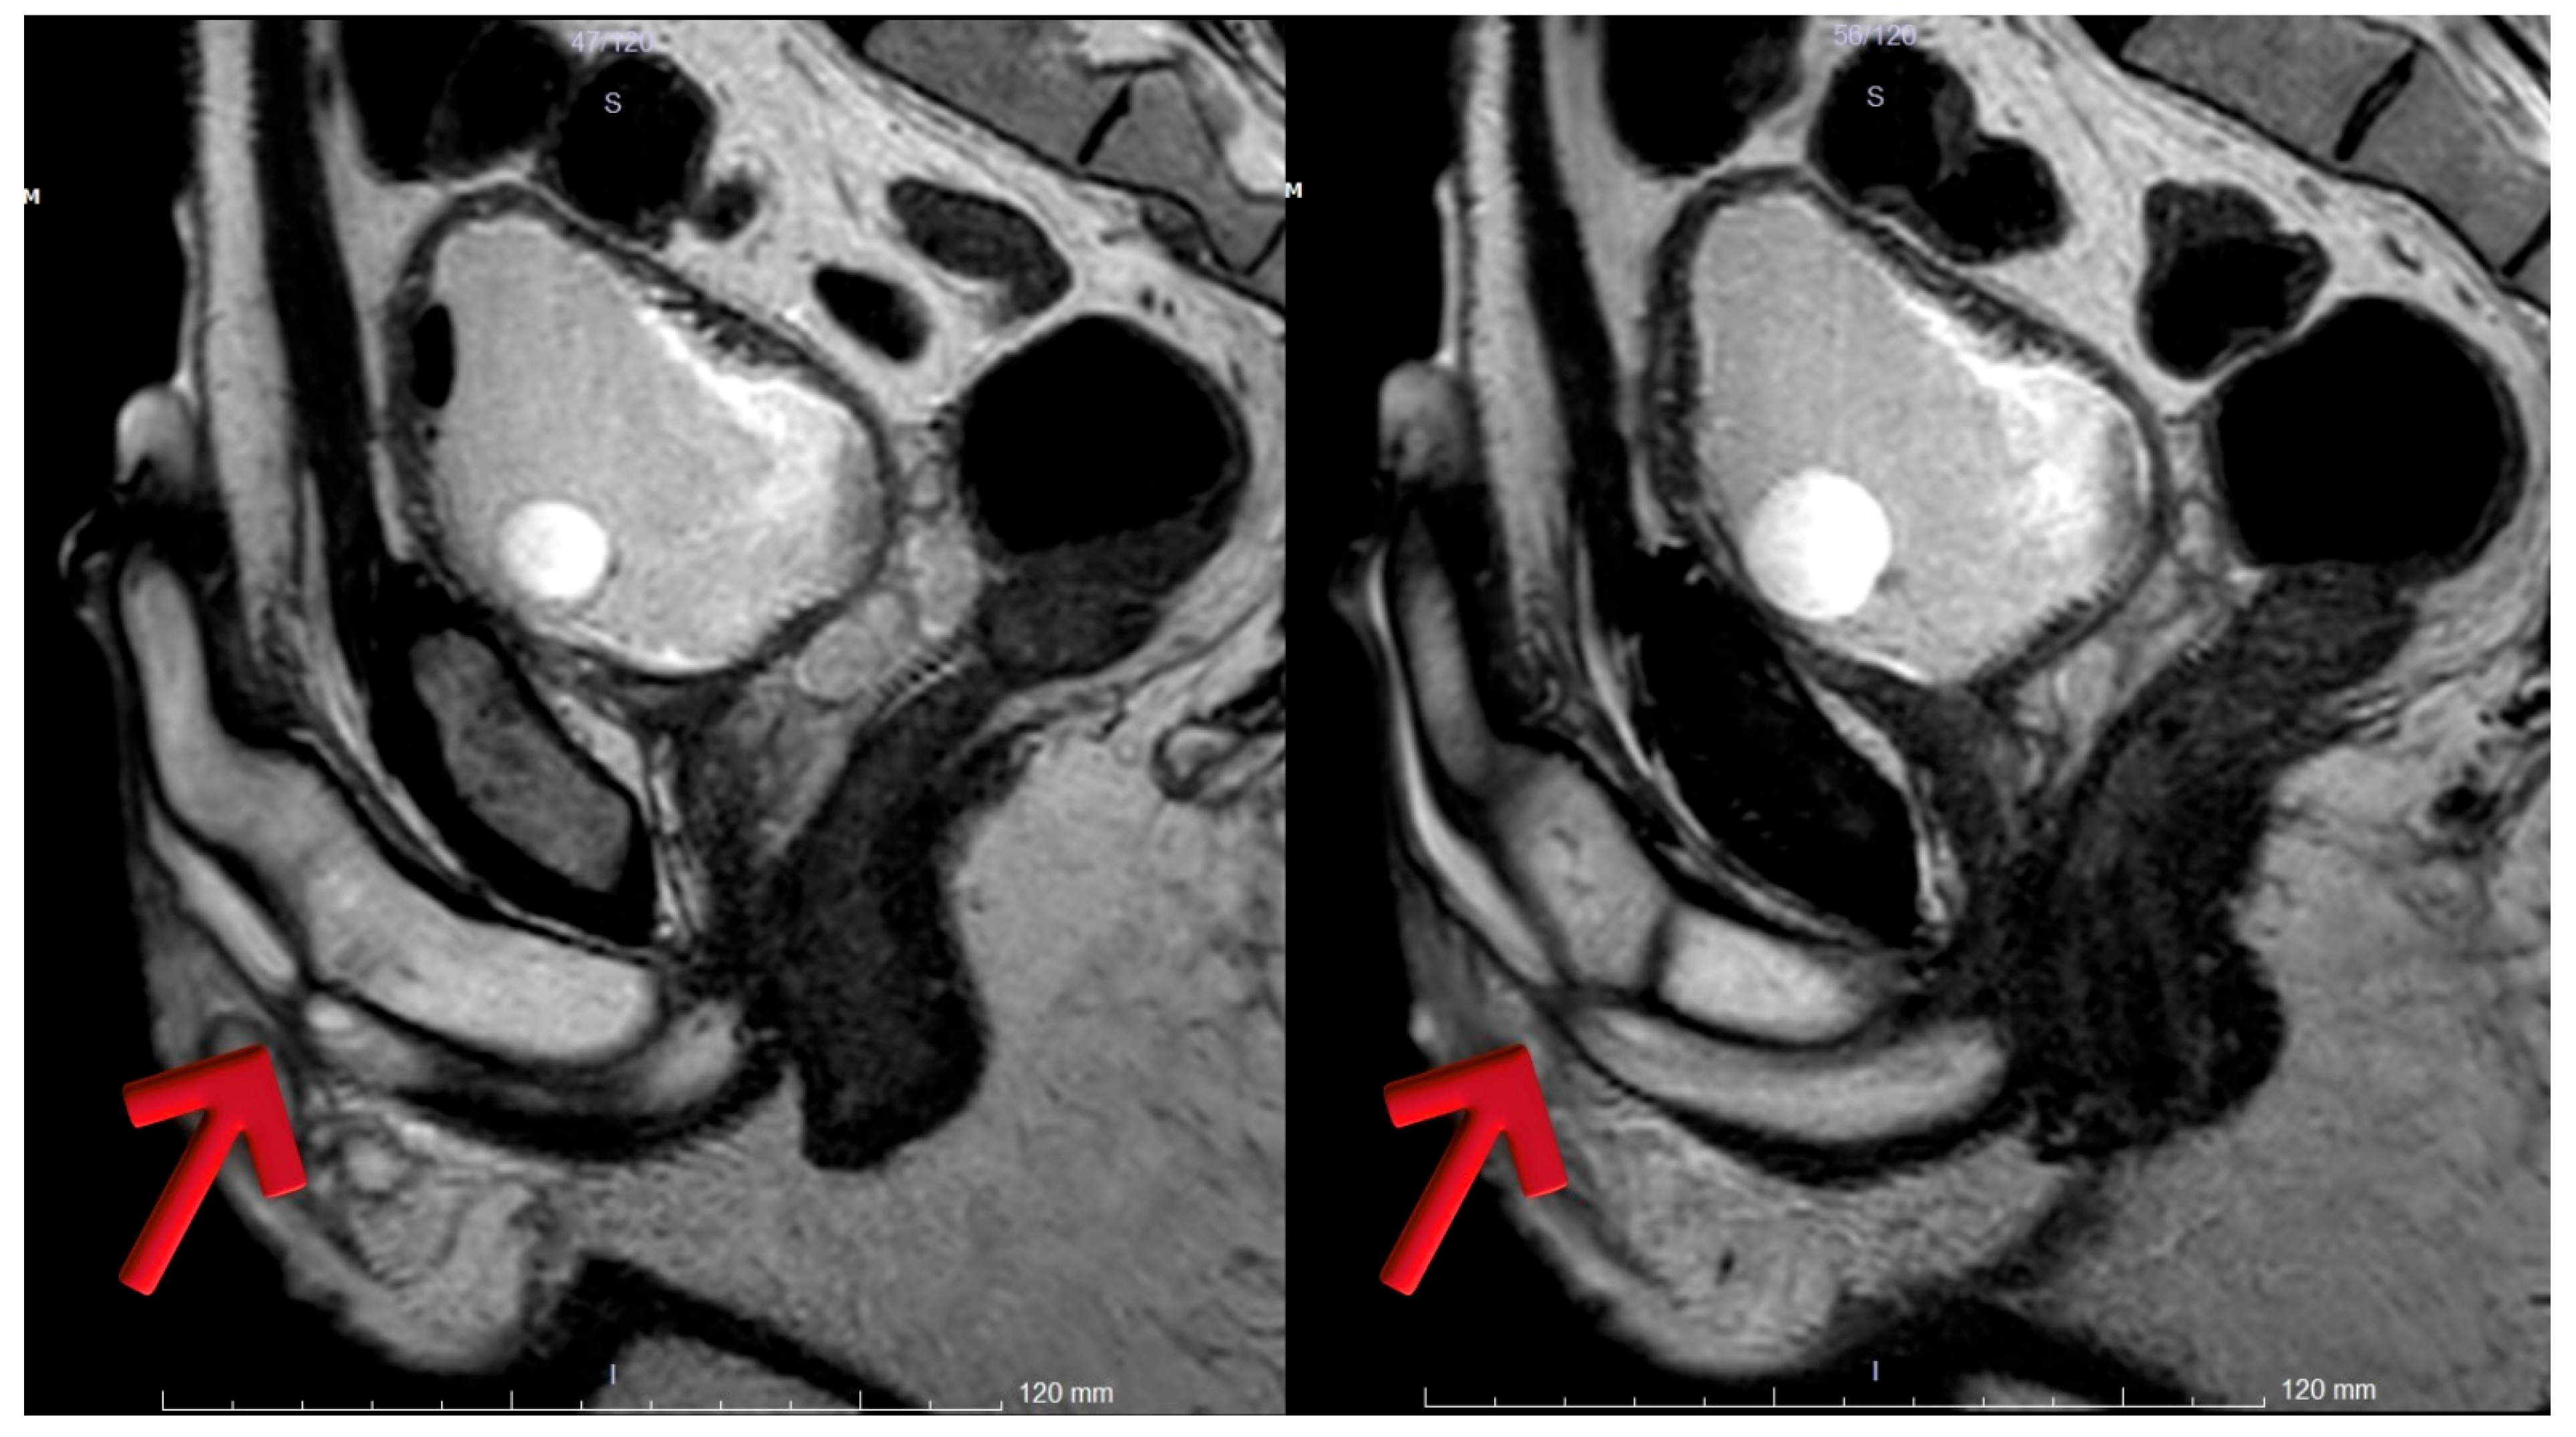

In MRI T1 and T2 imaging revealed two stricture areas in the distal bulbous urethra. Post-contrast, fat-suppressed T1a sagittal images demonstrated approximately a 2 cm lumen with moderate enhancement around the distal bulbous urethra, indicative of inflammation (Figure 3).

Figure 3. (A,B): T2-weighted sagittal images demonstrating complete obliteration at the distal bulbar urethra (arrows). (C): Post-contrast fat-suppressed T1-weighted sagittal image showing a narrowed lumen with surrounding inflammatory and fibrotic changes (arrow).